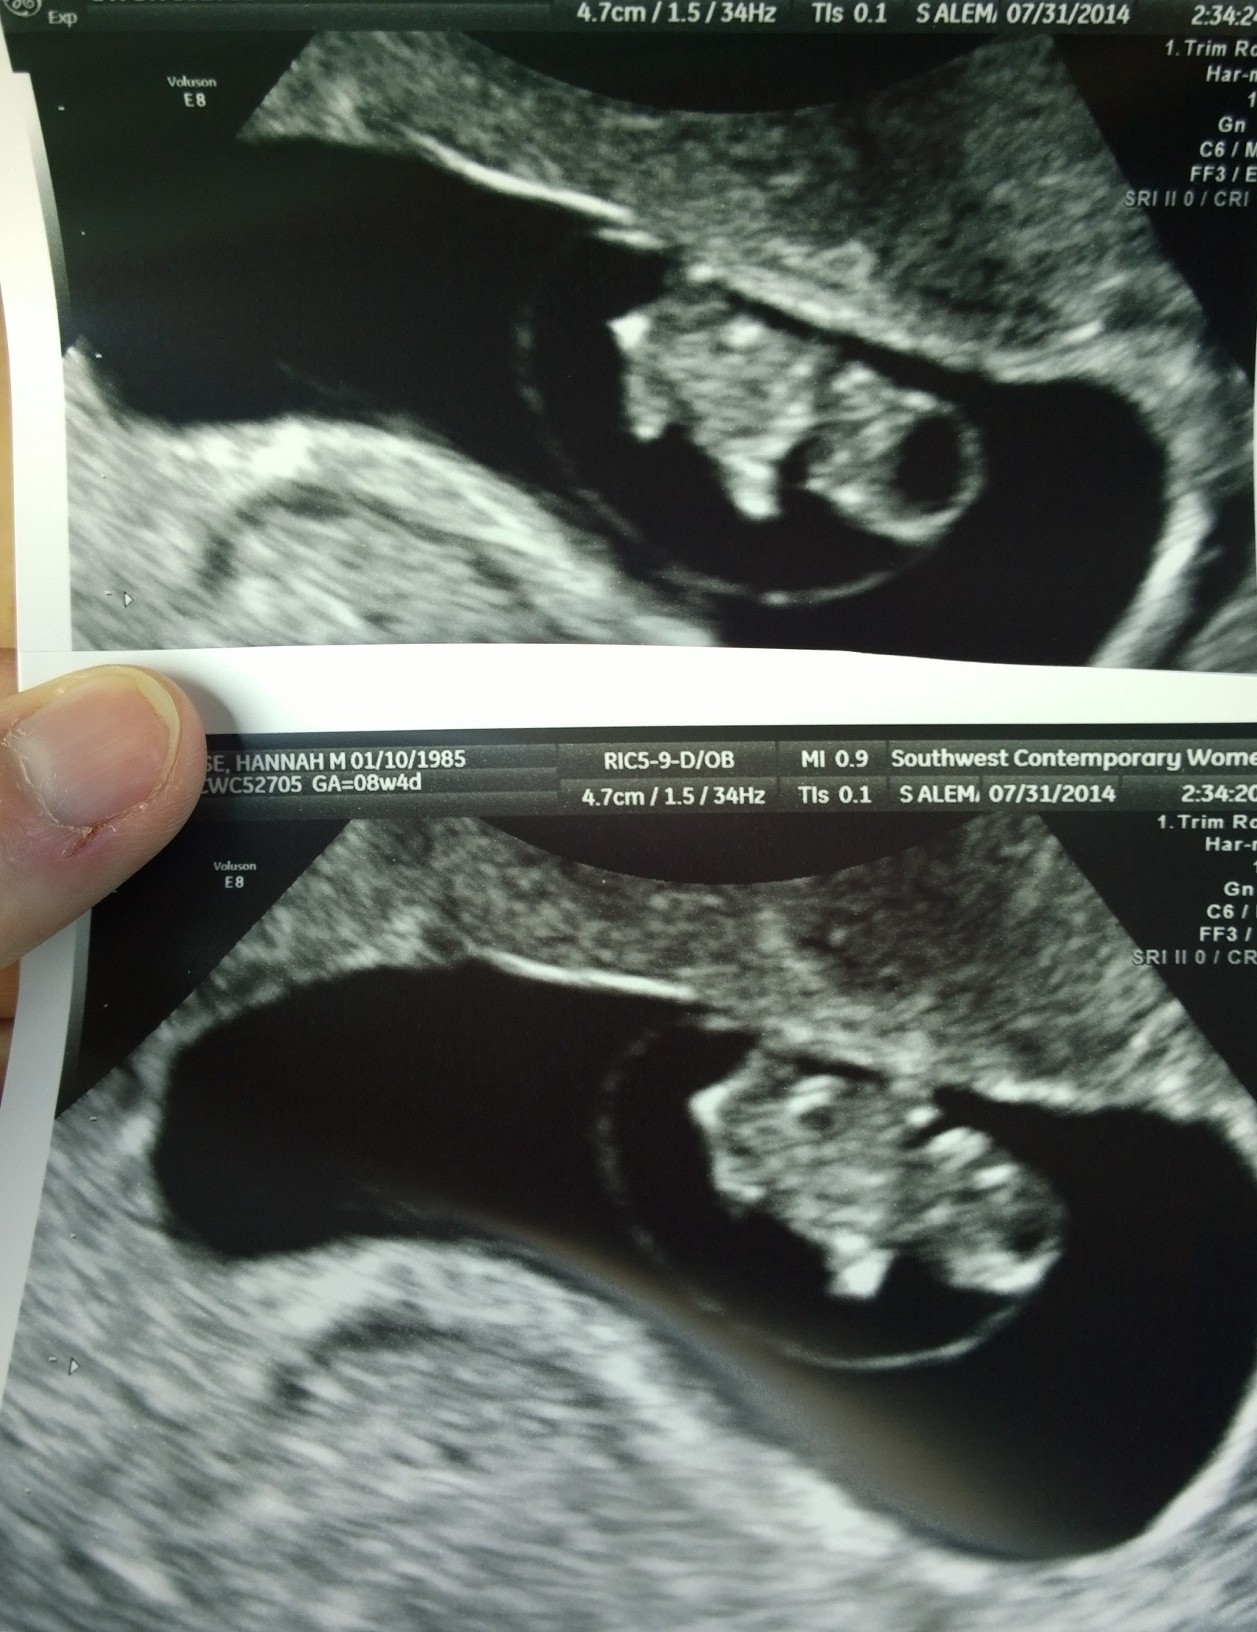

I am so relieved! Had an ultrasound this afternoon with my regular OB (instead of my RE) and saw my gummi bear! First thing I asked, was if there was a heartbeat! I saw the heart flickering and to my surprise, even heard it!!!!! 180 bpm, 1.76cm long!! The sac looked good, doctor even said it looked "robust". Baby is measuring 8w2d, the exact measurement when we miscarried back in March. And talk about awesome equipment, their equipment is soo much clear, newer and overall, BETTER than my RE!

I am so relieved, everything is looking so so good! Next appt is on the 28th!

Yeah, I couldn't believe how much clearer their machine is and how much they can zoom in. I feel more confident using their machine than my RE's.